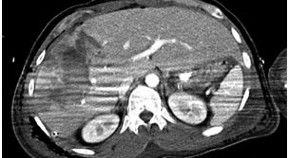

• This article considers the case of a 66-year-old white man who presented with a productive cough and pleuritic chest pain on his right side 6 months after undergoing transarterial chemoembolization for hepatocellular carcinoma. The patient was diagnosed with a biliopleural fistula, and this Case Study explores the diagnosis and management of this patient.

• Jeffrey R. Lewis

• Helen S. Te

• Smruti R. Mohanty